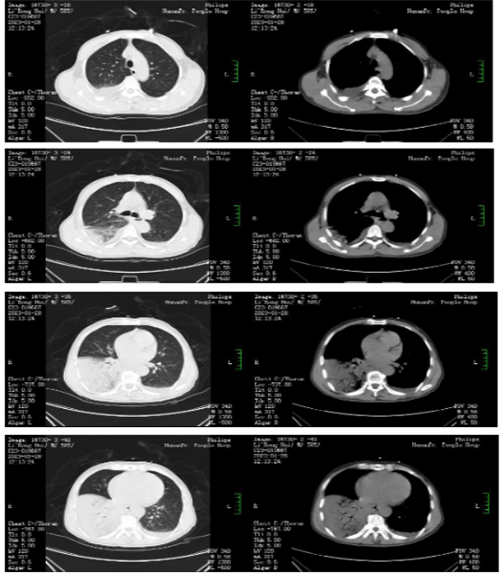

据其家人介绍,眼见着李叔叔情况不妙,他们赶忙将其送往当地医院检查,考虑重症肺炎,下了病危通知。经过几天的抗感染治疗,李叔叔的情况没有明显缓解,家人遂将其送往湖南省人民医院,收入全科医学科接受治疗。

李叔叔入院后,刘翠中主任组织进行了科内讨论,考虑李叔叔病程短、症状重,对当前抗感染治疗效果不佳,需要重点考虑少见病原体的感染,于是给李叔叔安排了支气管镜检查,并送检肺泡灌洗液进行宏基因组测序(mNGS:高通量测序,一种新的病原菌精准检测手段),最终明确感染的病原体是鹦鹉热衣原体。找到病因对症治疗后,李叔叔情况逐渐好转,并于2月23日出院。